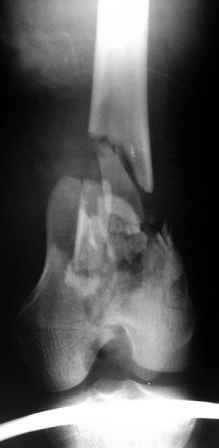

Рентгенограммы.

На рентгенограммах перелом не "н/3" бедра, что подразумевает диафиз, а перелом дистального суставного конца - крупные фрагменты мыщелков, метафиз фрагментирован, т.е. по классификации OTA/AO это 33C2.

По прямой проекции складывается впечатление, что метаэпифизарная часть бедра расколота вдоль и латеральный мыщелок смещен книзу. Интрамедуллярный штифт "повиснет" между мышелками и есть вероятность, что при раннем начале движений мыщелки "разойдутся". Учитывая, что рана зажила первичным натяжением, предпочел бы пластину с костной пластикой. запасной вариант - аппарат Илизарова.